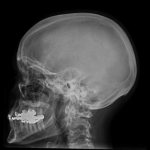

Центральная нервная система разделяется на спинной и головной мозг. Эти структуры сформировались эволюционным путем от низших простых, до высших и сложных структур.

Головной мозг состоит из таких отделов (от низших к высшим структурам):

- Продолговатый мозг – продолжение спинного мозга.

- Задний мозг: мозжечок и Варолиев мост.

- Средний мозг: подкорковые центры слуха, зрения, транзиторные пути между спинным мозгом и корой.

- Промежуточный мозг: таламус, гипофиз, гипоталамус.

- Конечный мозг – кора полушарий. Выделяют такие зоны: лобную, теменную, затылочную и височную.